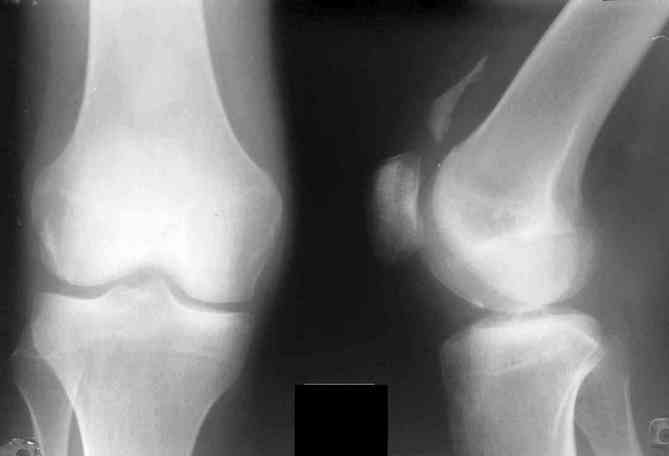

С помощью рентгенографии можно выявить признаки поражения суставов — сужение суставной щели, эрозии костных поверхностей. На выполненных в двух проекциях снимках визуализируются пяточные шпоры, паравертебральная оссификация, периостит костей стоп. В большинстве случаев не требуется проведение артроскопии.

Для более детального изучения суставных структур иногда назначается МРТ, позволяющая оценить состояние хрящей, мышц, связочно-сухожильного аппарата, нервных стволов, кровеносных сосудов.

Рентген коленного сустава